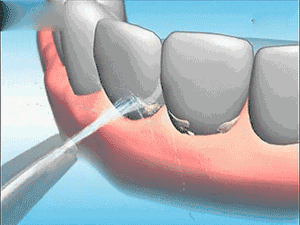

因为洗牙,是去除牙菌斑和牙石特别有效的方法。

洗牙不但可以改变你的生活,而且可以防止你美好的生活被改变。

每半年到一年洗一次牙,可有效预防牙周疾病,有助于保持口腔健康。

牙石的堆积、牙龈的炎症会导致牙龈的局部肿胀填塞牙缝,而洗牙后去除了牙石,牙龈肿胀逐渐消退,所以牙缝就变得明显了,其实这是牙齿的真实面目,绝非洗牙所造成的。

洗牙会把牙石去掉,这样就终止了牙周炎的进展,让牙齿不再继续松动下去。